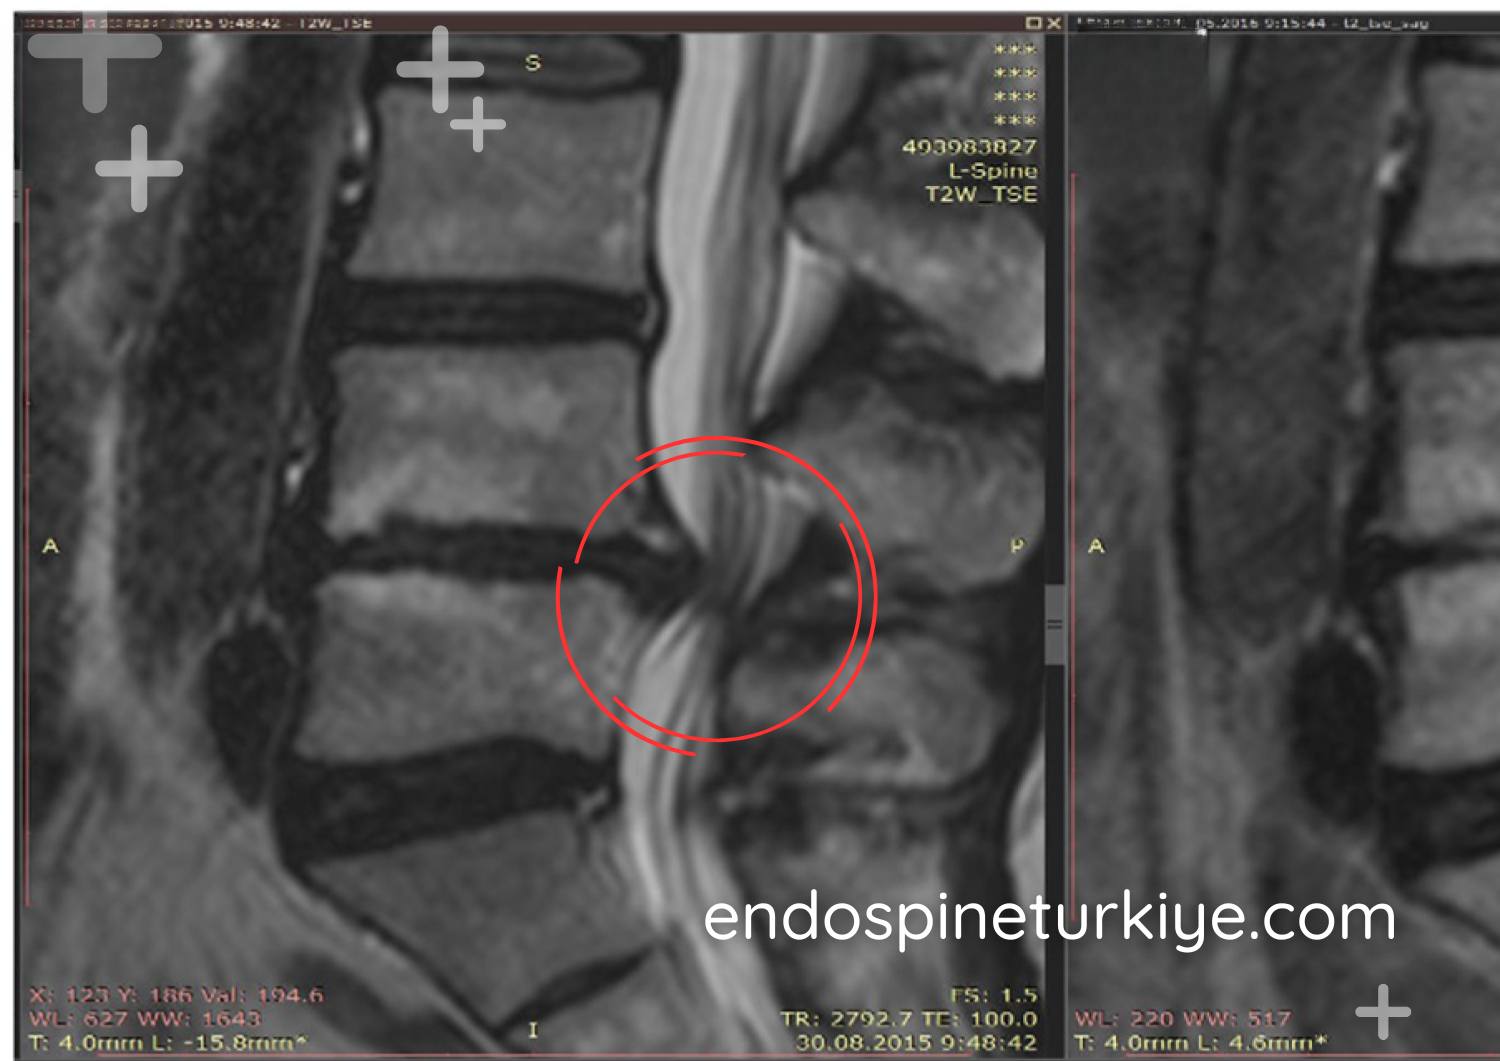

Bel Fıtığı Ameliyatı Öncesi ve Sonrası

Tedavi Öncesi

Tedavi Sonrası

MR görüntülerinde endoskopik bel fıtığı ameliyatı öncesi ve sonrası karşılaştırma